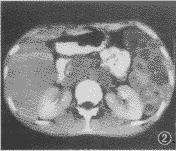

图2 同图1病例,CT增强。见病灶无强化,边界清楚